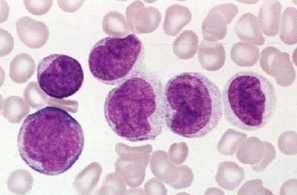

Acute monocytic leukemia (AML-M5)

- 最常侵犯口腔的 leukemia

- 血小板減少 → 出血

- 病灶在骨隨

- 腫瘤細胞增生,取代正常細胞甚至破壞骨質